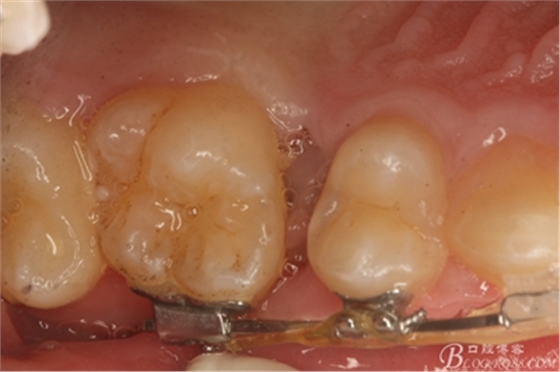

圖2.從合面觀:16與14之間的牙間隙牙齦顏色異常,建議拍根尖片。